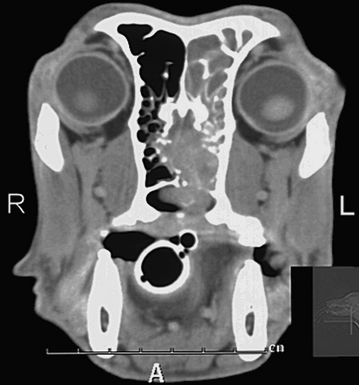

Signs Of Nasal Cancer In Dogs - Nasal Cancer in Dogs - Symptoms, Causes, Diagnosis ... - The first signs may be very.. Understanding the signs of cancer can help you save your dog's life. Nasal passage cancer generally develops very insidiously in older pets, so find out the signs of this disease and how to treat it. Though, this cancer symptom is much more alarming for an older dog than it for younger dogs, nosebleeds could occur when the there are foreign objects blocking the nasal airways. The signs of cancer in dogs vary depending on the type of cancer and how advanced it is, but dr. At first, the nasal discharge might look like nothing more than a.

You may notice a decrease in your dog's appetite. They are thirsty but cannot drink much. The nasal cavity in dogs and cats is a complex structure consisting of nostrils that open up in two air passages. The discharge may contain mucous, pus, and blood. Signs of nasal cancer in dogs are abnormal discharge, bleeding, snoring or trouble breathing. For example, a bone tumor (osteosarcoma) might cause a limp, or a bladder this bleeding causes sudden weakness and wobbly legs. Nose cancer (or nasal adenocarcinoma) occurs when too many cells in the animal's nasal and sinus passages come together. Weight loss is the number one sign of cancer in dogs. Because nasal cancer tends to affect mostly one nostril, any discharge that appears to come out of one nostril and appears to be of a mucus, thick/creamy consistency and that is green, yellow, or sometimes bloody, should. It has been speculated that dolichocephalic breeds or dogs living in urban environments. Nasal tumors make up approximately 1% of all cancers seen in dogs. The most common type of cancers affecting the animal's nose are carcinomas and sarcomas, both of which are locally invasive. Skin cancer, bone cancer, and internal cancers claim the lives of many dogs.

A serious disease followed by growing some cells anomaly. Two veterinarians discuss nasal tumors and what you can do if your dog has been diagnosed with cancer in the nasal region. Other examples of cancerous tumor types include salivary gland cancer, sarcoma, esthesioneuroblastoma, lymphoma, sinonasal undifferentiated carcinoma, and melanoma. What should you tell owners? Nasal cancer usually occurs in the form of squamous cell carcinomas or fibrosarcomas in dogs. Vets talk about the signs of cancer in dogs. So now (finally!), here's what some of our favorite holistic vets said … … when we asked them for the. Studies have shown nose cancer is more common in larger animal breeds than in smaller ones, and it may be. Early cancer detection in dogs can be tricky due to their inability to communicate with their caretakers in a clear language. For example, a bone tumor (osteosarcoma) might cause a limp, or a bladder this bleeding causes sudden weakness and wobbly legs. Lachowicz point to three key indicators and then the specific signs can be anything from respiratory issues, like coughing, sneezing, nasal discharge; What are the symptoms of nasal cancer in dogs? The most common sites for metastasis are the lymph nodes and the lungs, but can also include other organs.

What are the signs of a nasal tumor? For example, a bone tumor (osteosarcoma) might cause a limp, or a bladder this bleeding causes sudden weakness and wobbly legs. The type of tumor is a reflection of the parent tissue from which it grew. When you adopt a puppy and bring home the newest canine companion of your family, the dream is to one of the most telling signs of cancer in the nose of dogs is nasal discharge. Signs of nasal cancer in dogs are abnormal discharge, bleeding, snoring or trouble breathing.